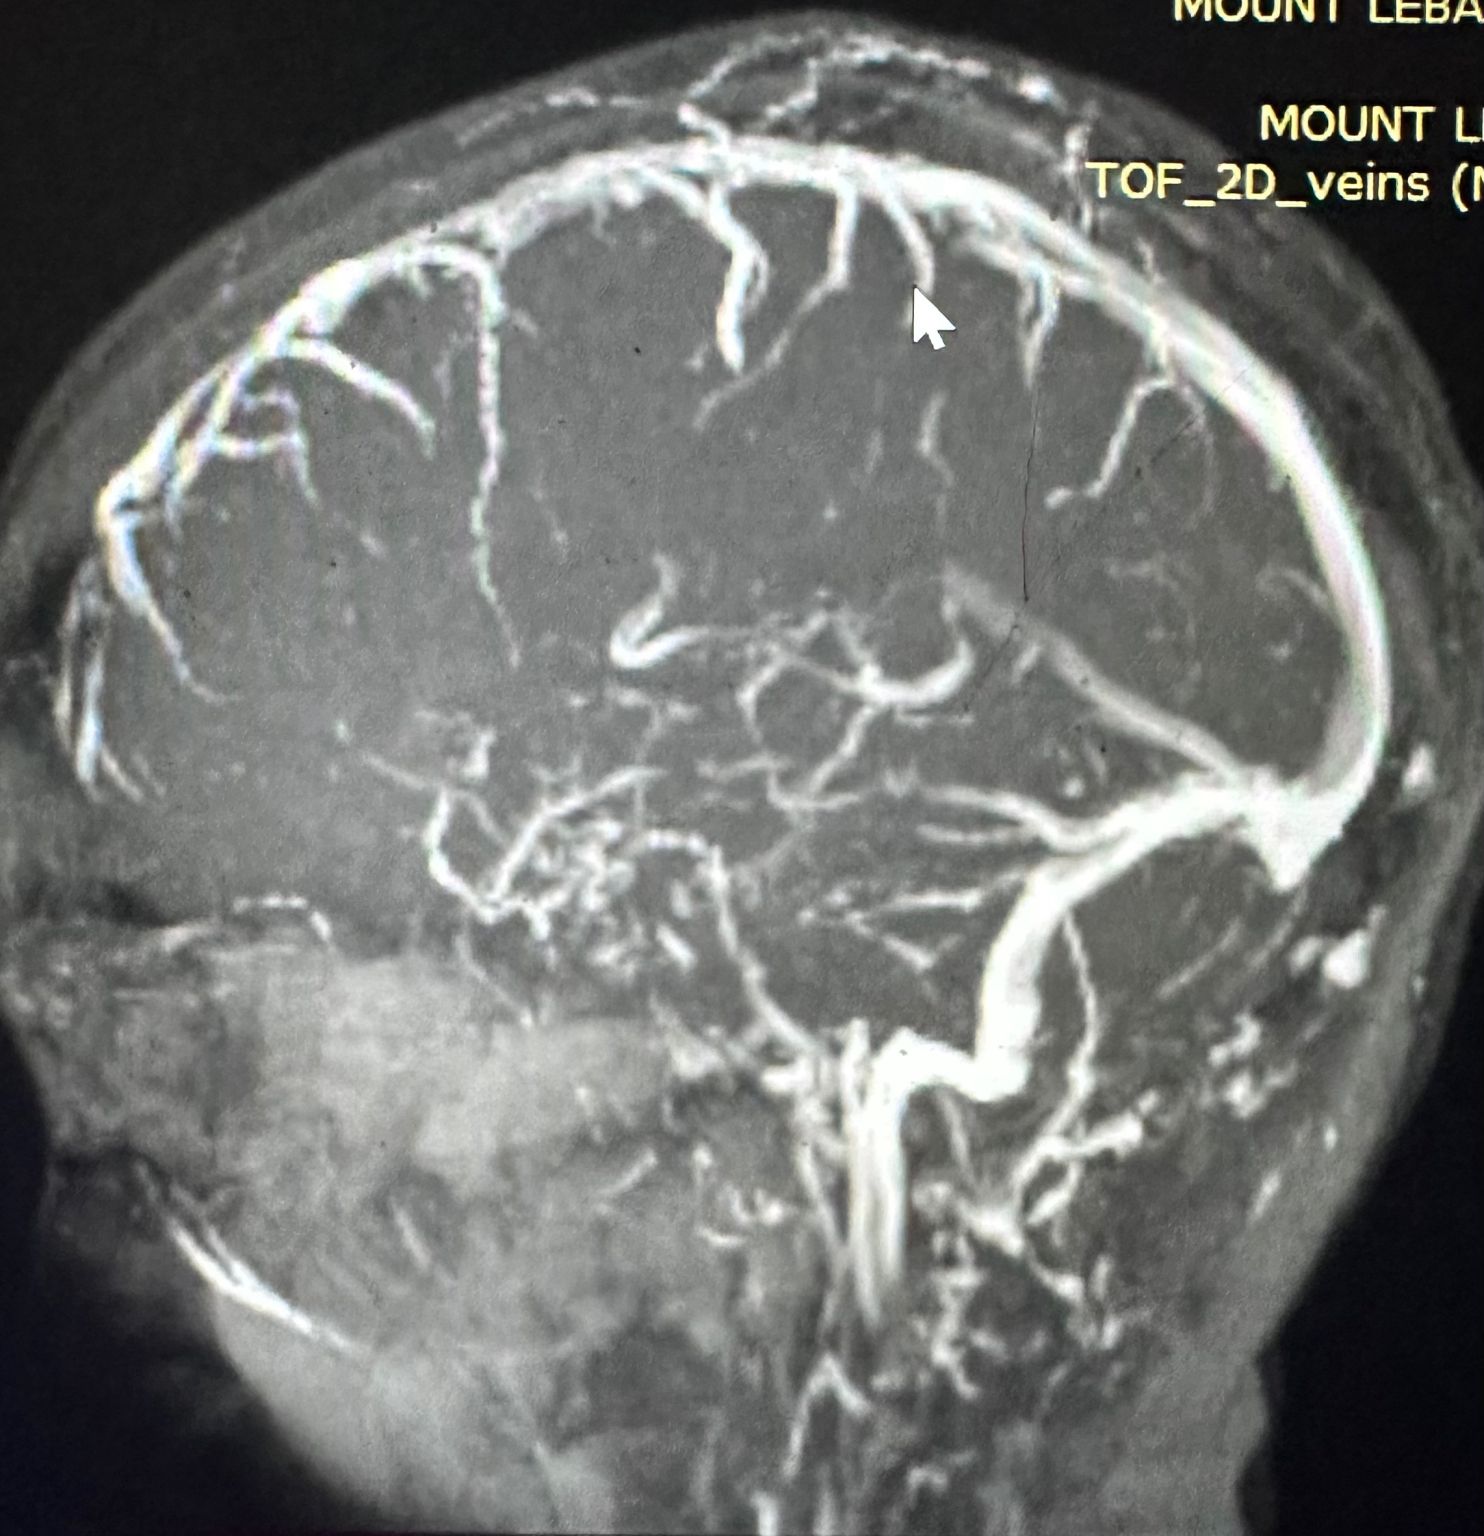

Meningioma Surgery

Middle Cranial Fossa Meningioma Resection

Performed gross total resection of a large meningioma invading the right transverse sinus. The sinus was opened, tumor removed, and sutured microscopically while preserving the Galen’s vein. Postoperative anticoagulation managed with Lovenox and Rivaroxaban. The patient remains seizure-free and in excellent condition.